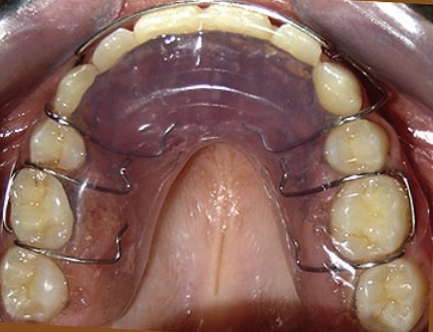

La férula de retención acrílica se fabrica con la configuración de los dientes en boca tras realizar el tratamiento de

ortodoncia. Se realiza sobre unos modelos tomados tras el tratamientos. Este apararato se ajusta perfectamente en la arcada dental del paciente y es necesario llevarlo las horas que indique el profesional. Al ser semirrígido mantiene los dientes en su lugar. Al ser transparente la estética es buena